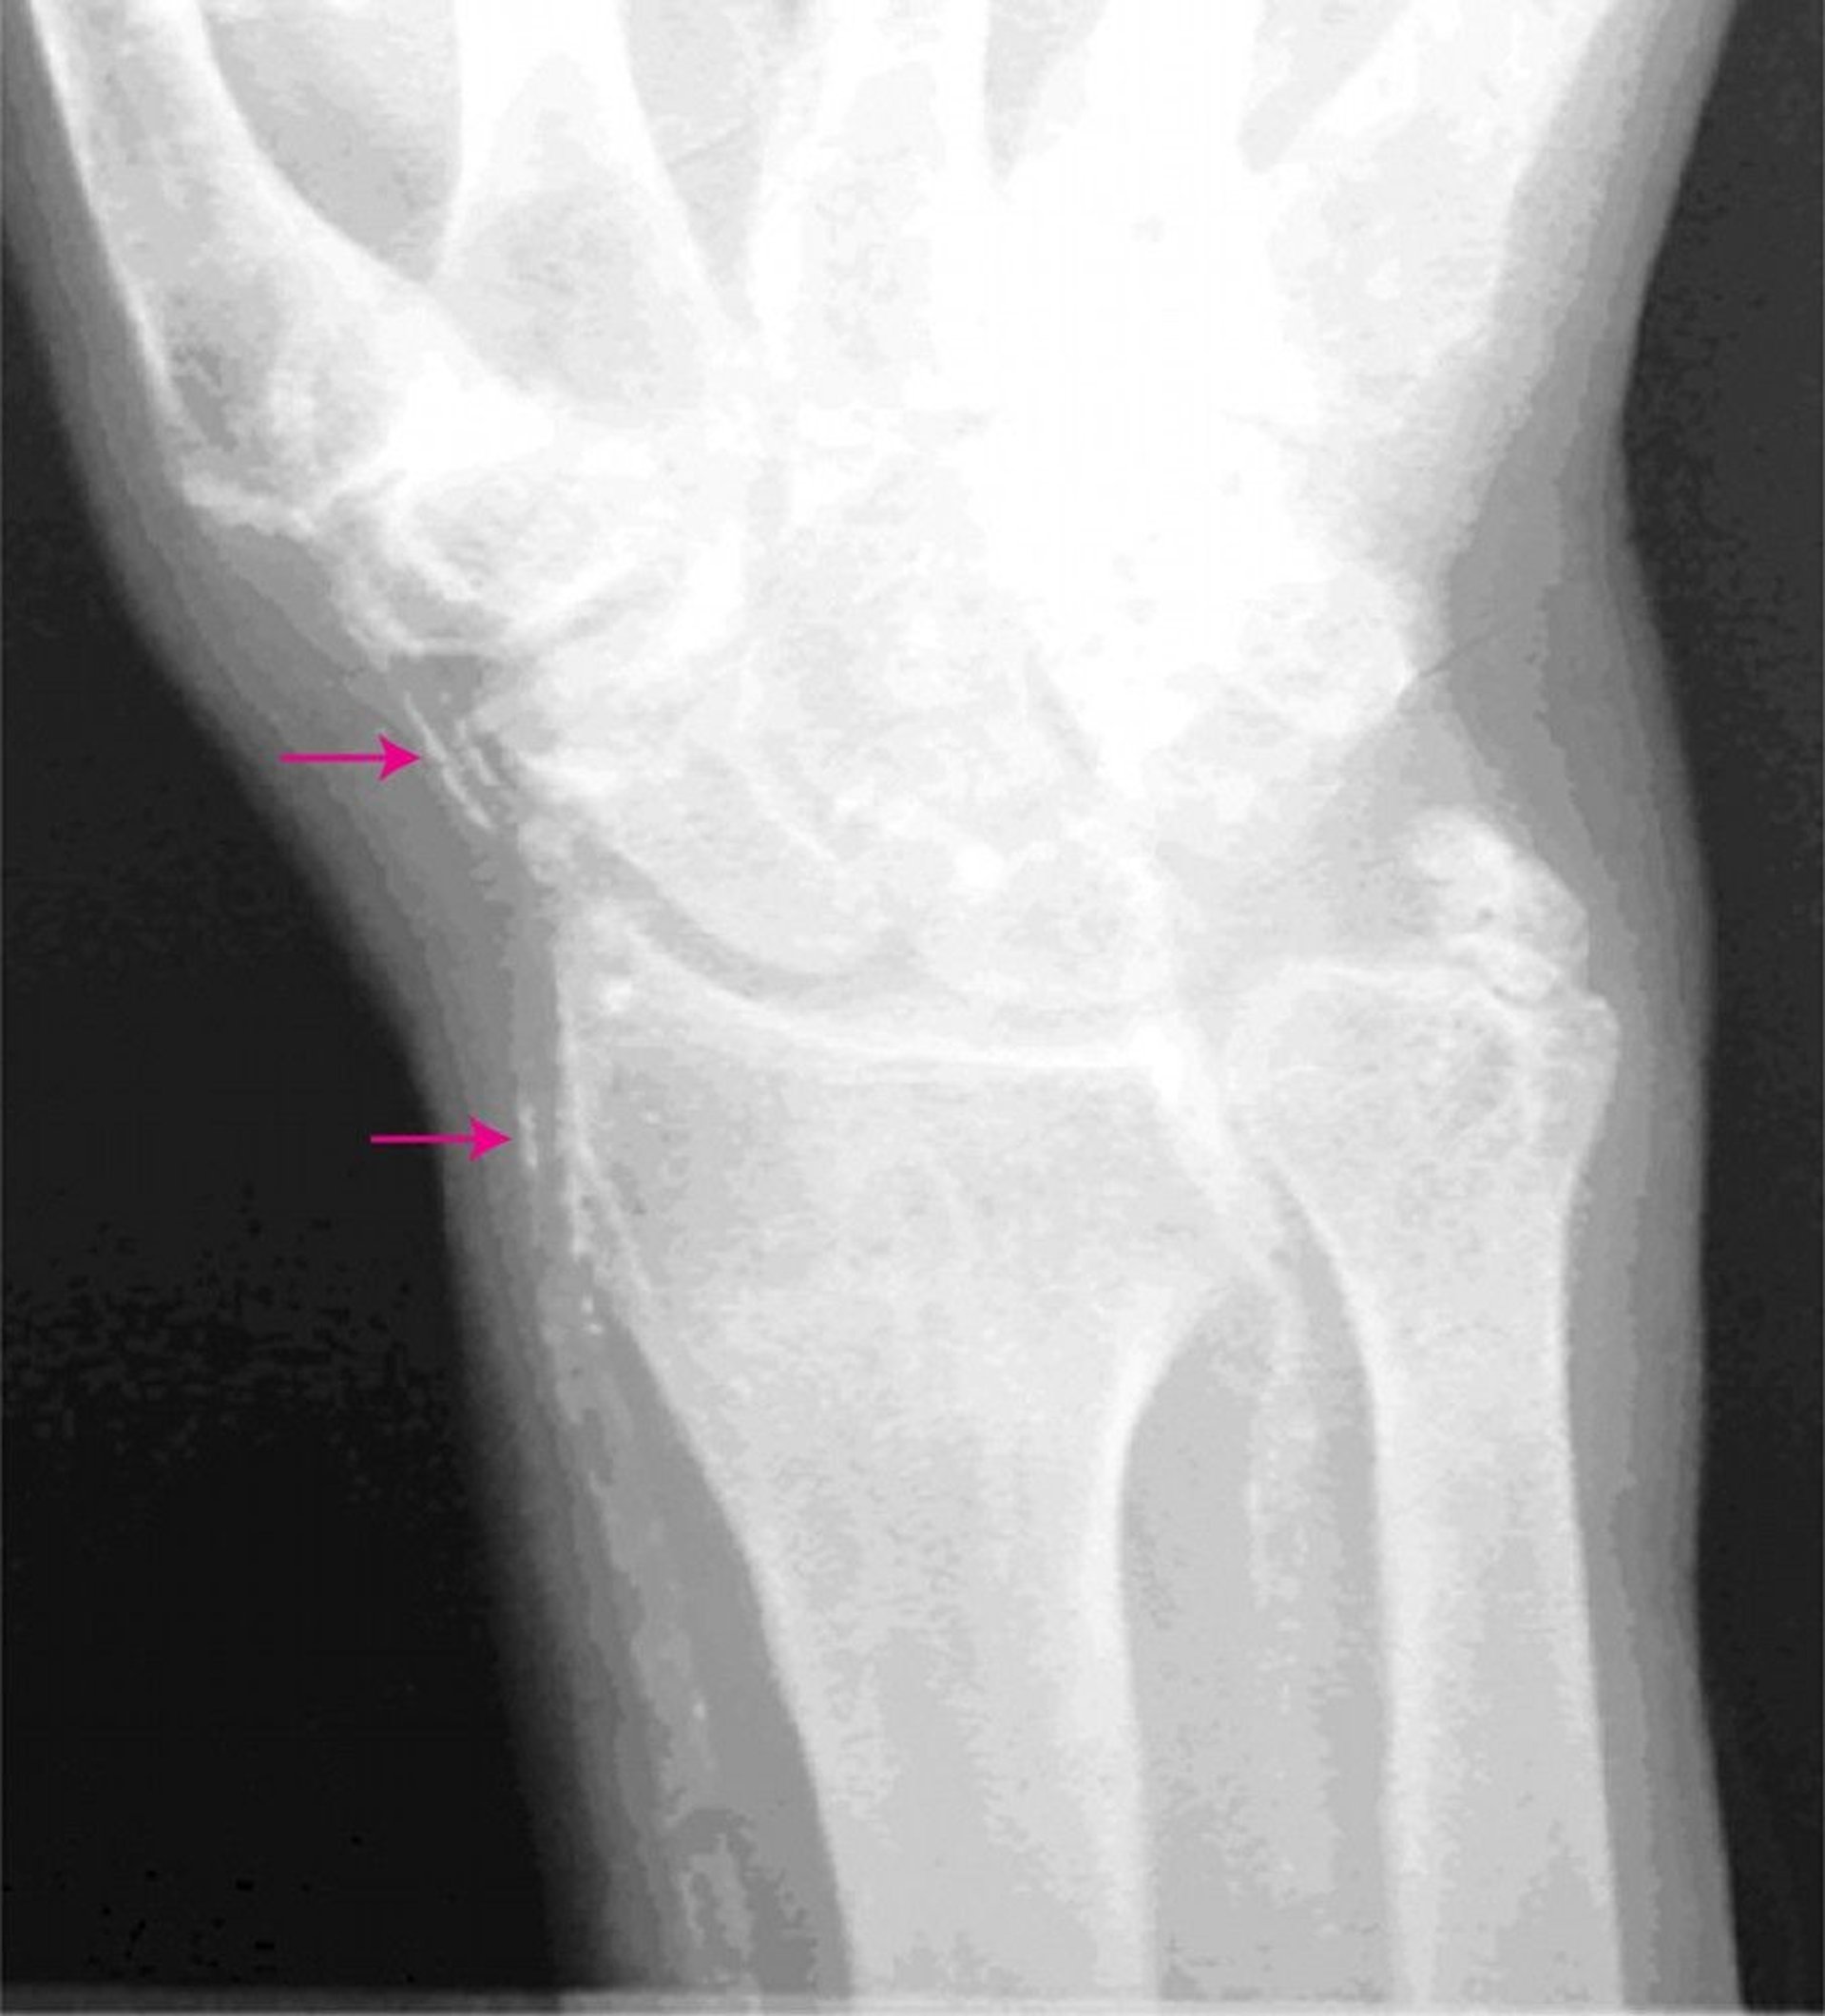

Mönckeberg Medial Calcific Sclerosis

This radiograph of the hand shows calcified arteries (arrows).